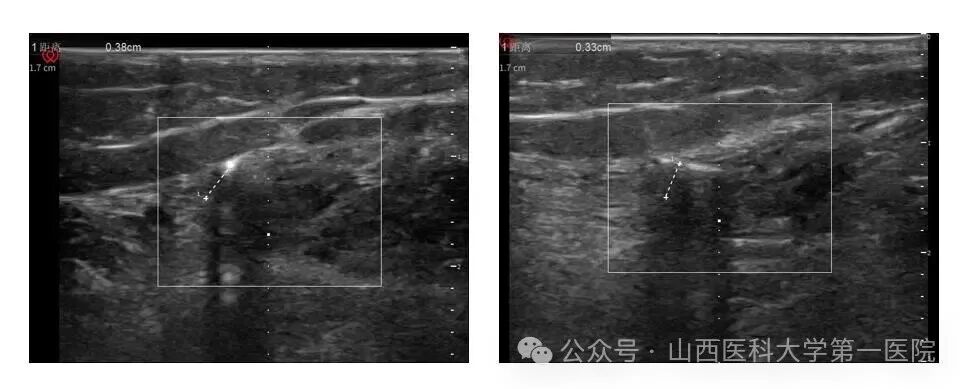

泌尿外科任力娟副主任医师团队运用国际领先的微创技术,为长期饱受难治性膀胱过度活动症折磨的患者武女士成功实施了山西省首例创伤最小的胫神经刺激器植入术,在局部麻醉下通过长约0.5厘米的微小切口,以0.2厘米的精准距离刺激胫神经,术中刺激应答良好,整个手术过程用时约15分钟。

任力娟介绍到,本次手术在科室主任曹晓明和手术室护士长田华的精心安排下,在麻醉科副主任医师井子夜精准超声定位以及手术室吴琼、王钟皎两位护士协助下顺利完成;植入式胫神经刺激疗法通过精确定位,将微型刺激器植入踝关节胫神经附近,创伤极小、手术时间短,为开展日间手术提供了有力支撑,具有显著优势和技术突破性,希望该疗法能早日通过临床试验,惠及更多尿失禁患者。未来团队将持续优化方案,力争让90%符合适应症的患者实现“当天手术、次日恢复正常生活”的目标。”